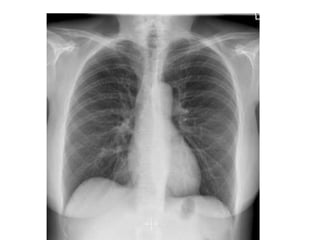

BASIC TISSUE RADIOGRAPHIC

OPACITIES

1. GAS - BLACK

• MOST RADIOLUCENT MATERIAL VISIBLE ON

FAT -GREY

• MORE LUCENT THAN BONE AND SOFT TISSUES

BUT IS MORE OPAQUE THAN AIR

SOFT TISSUE /FLUID- LIGHT WHITE

• BOTH SOFT TISSUE AND FLUID HAVE SAME

RADIOLUCENCY. VARIATION IN VOLUME ,

THICKNESS AND DEGREE OF COMPACTNESS

OF SOFT TISSUE CREATES A PATTERN OF

VARIOUS DENSITIES ON THE RADIOGRAPH

BONES & MINERAL- WHITE

• BONE IS COMPOSED PRIMARLY OF CALCIUM

AND PHOSPHOROUS

• NORMAL VARIATION IN THE RADIOPACITY

WITHN THE BONE AND BETWEEN BONES

BECOZ OF DIFFERENCE IN RADIOPACITY OF

COMPACT V/S SPONGY BONE ,CORTICAL V/S

MEDULLARY CANAL

METAL –BRIGHT WHITE

• MOST OPAQUE SHADOW SEEN ON

RADIOGRAPH